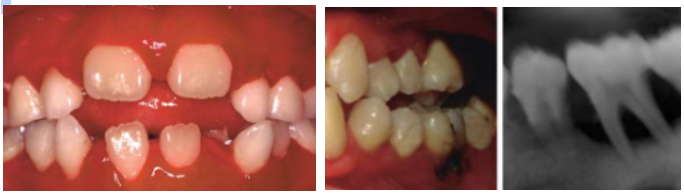

Primary herpetic gingivostomatis

Primary Herpetic Pharyngotonsilitis (in adults)

Intraoral secondary herpes infection

Seen only on the hard palate and gingiva

Exception to this rule is in AIDS patients, in whom herpes may occur on any mucosal site)

Herpes labialis

most secondary herpetic lesions occur on the vermilion & perioral skin. These patients have lip discomfort but no systemic signs or symptoms.